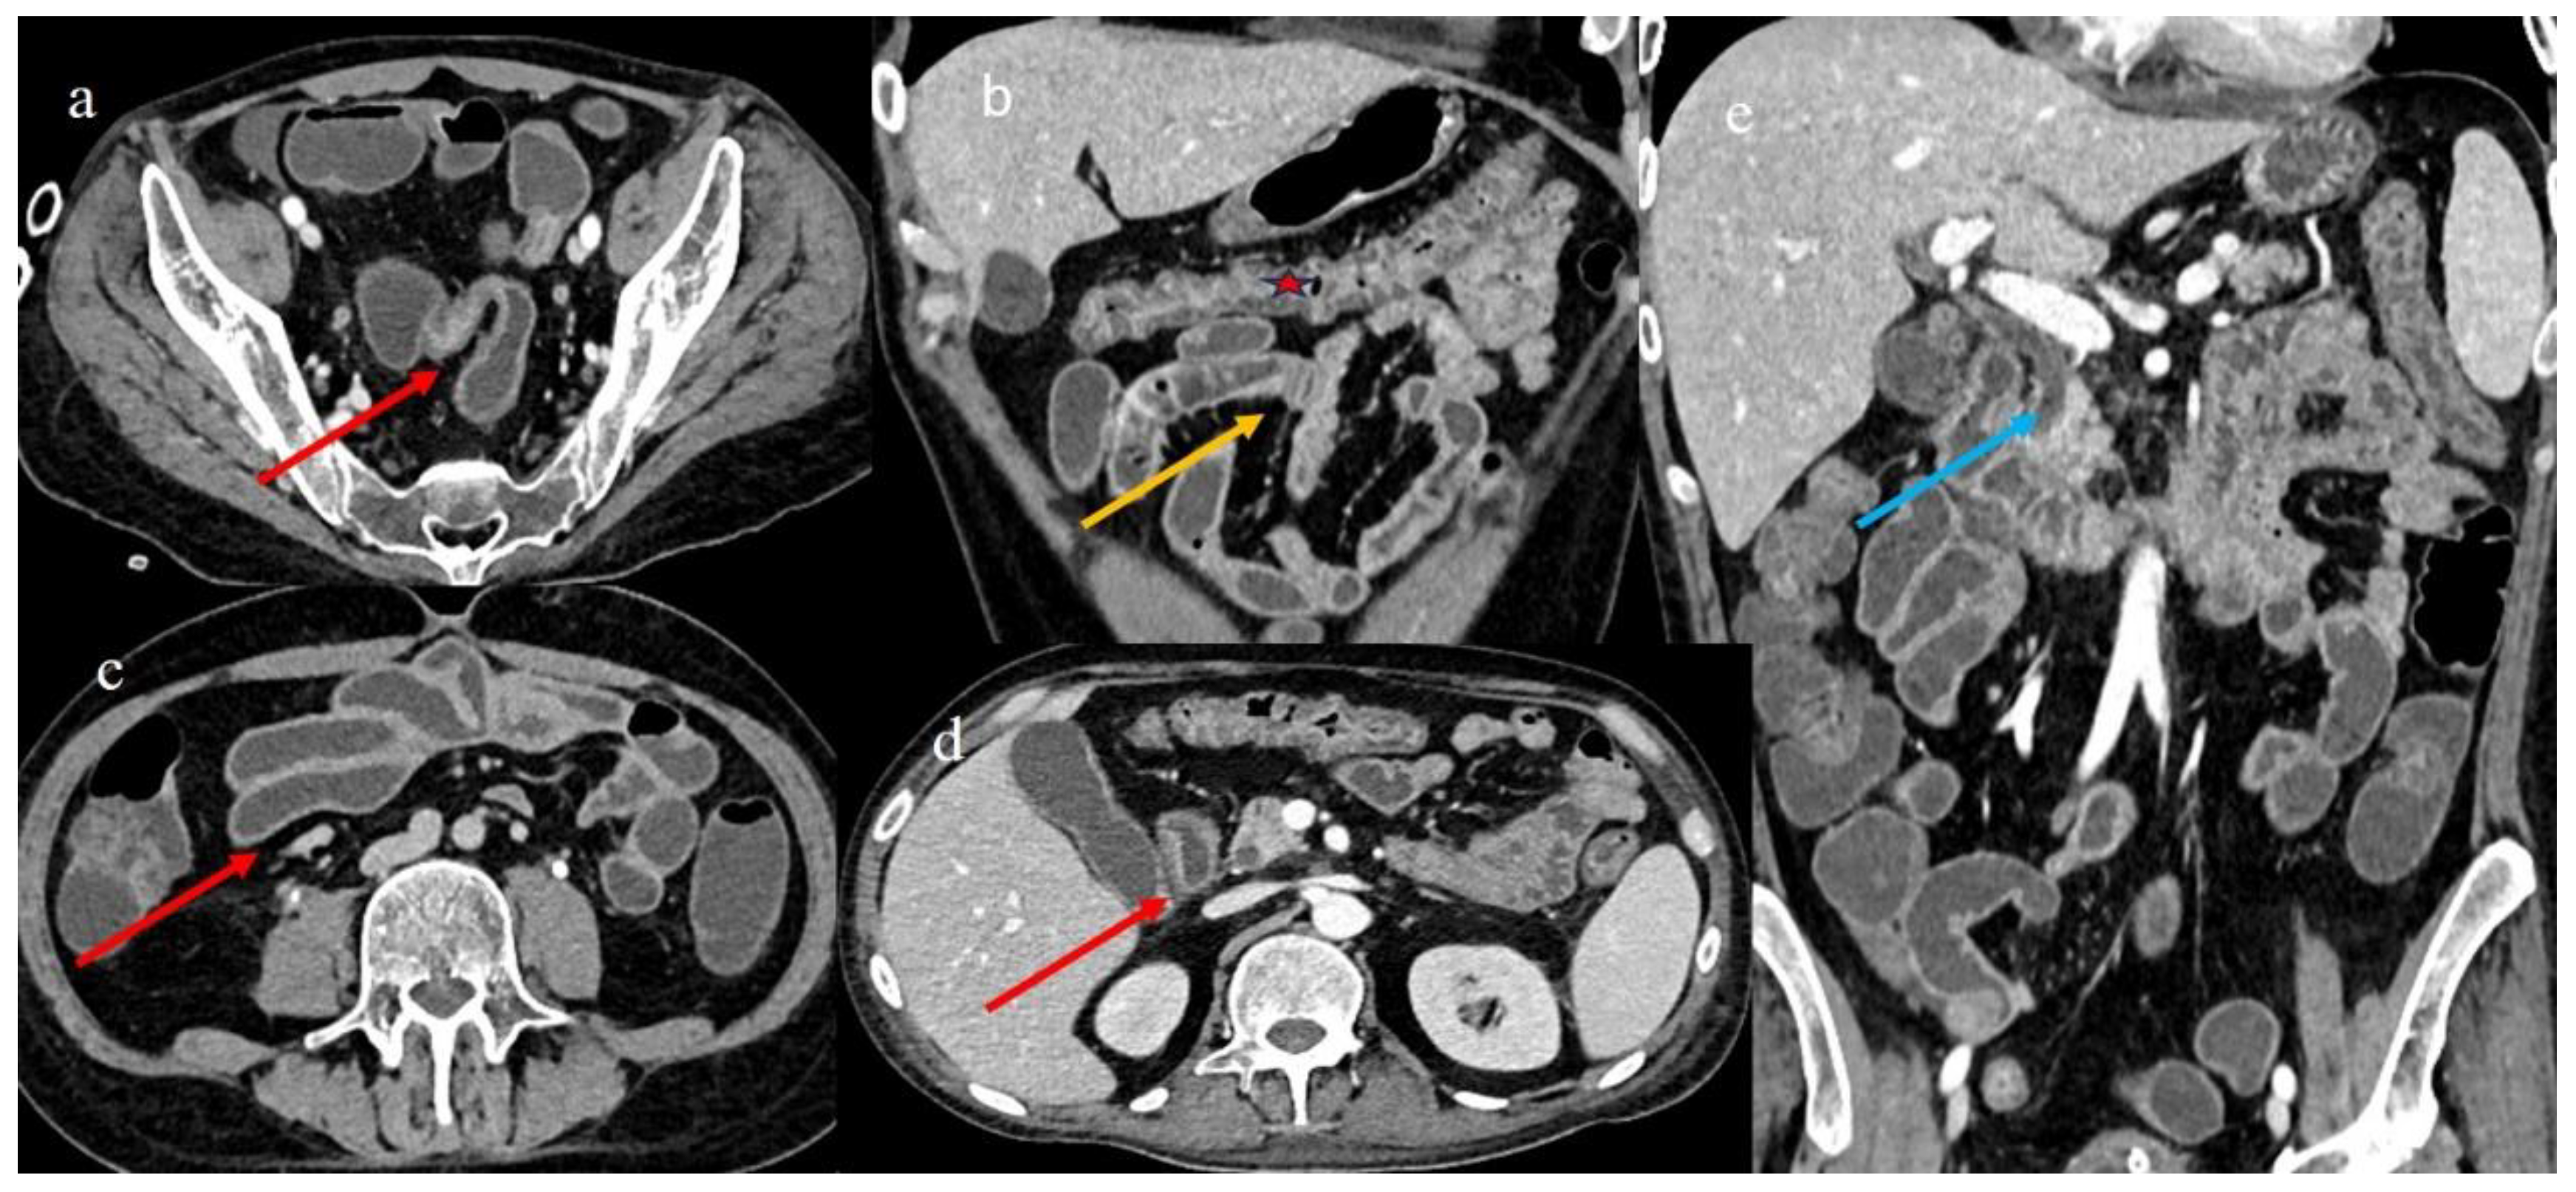

| 5 | P | P | Multisegmental thickness with stenosis on jejunal loops and SBO and segmental and focal thickness on the terminal ileus and appendix | Diffuse parietal thickness with stratified enhancement | Mild comb sign, poor reactive mesenteric lymph node, small air bubbles in the ascites | Small splenic areas of ischemia |